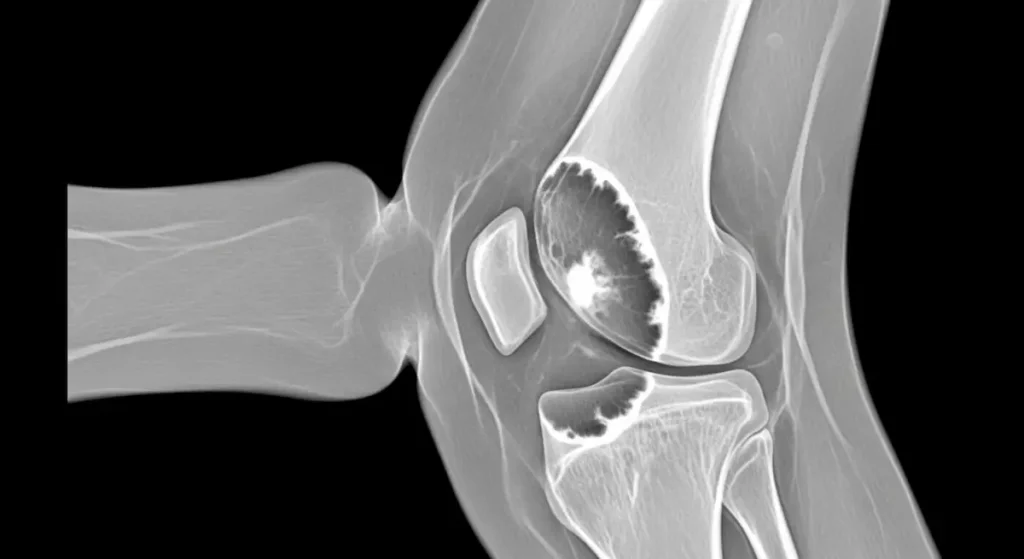

O tumor de células gigantes do joelho é uma lesão óssea, em geral benigna, que costuma aparecer na junção metaepifisária do fêmur distal ou da tíbia proximal.

Ao microscópio, reúne células estromais e células gigantes multinucleadas, parecidas com osteoclastos. Esse perfil histológico explica as áreas de reabsorção que aparecem nos exames de imagem.

- A radiografia costuma mostrar lesão lítica excêntrica na epífise, por vezes com adelgaçamento cortical.

- A ressonância magnética delimita extensão intraóssea e comprometimento de partes moles.

- A tomografia auxilia no planejamento cirúrgico e na pesquisa de metástases pulmonares.